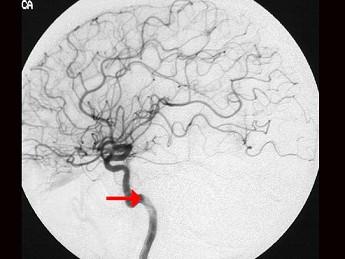

问题 如图箭头所示为大脑哪根动脉 ( )

选项 A、基底动脉 B、大脑后动脉 C、颈总动脉 D、大脑中动脉 E、颈内动脉 一、单项选择题

答案 E